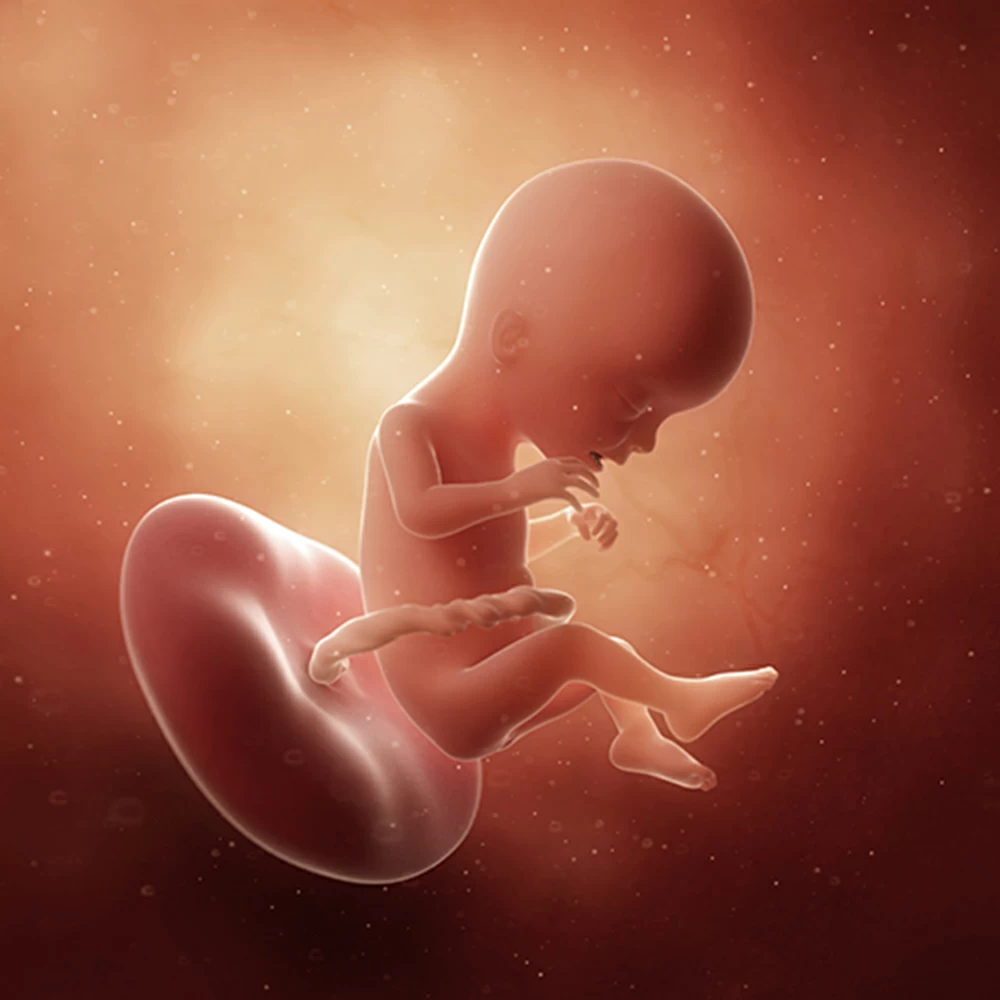

Неделя № 21

Масса тела вырастает до 380 грамм, длина плода – до 27 см.

Плод свободно перемещается в полости матки: ложится вниз головой или ягодицами, поперек матки. Может играть пуповиной, отталкиваться руками и ногами от стенок матки.

Изменяется режим сна и бодрствования. Сейчас плод меньше проводит времени во сне (16-20 часов).